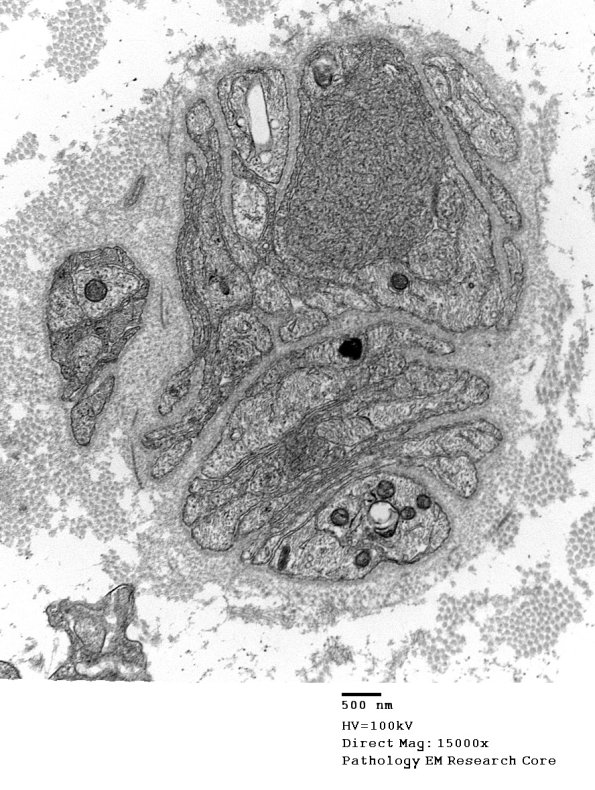

Case 2 No History ---- 2A1,2 Classical dystrophic axon with tubulovesicular elements. (electron micrographs)